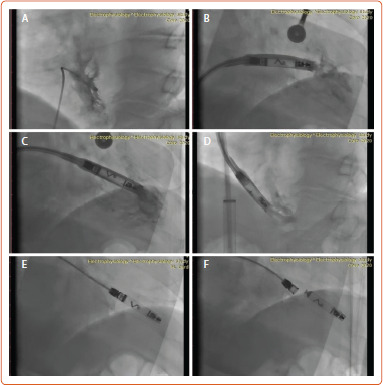

In this article, we describe our first experiences implanting the AVEIR VR leadless pacemaker (Abbott) in Kazakhstani patients, a significant step in the development of this technology in Central Asia. This case series includes five male patients, with a range of symptoms (presyncope, dizziness and dyspnoea on exertion), ranging in age from 14 to 77 years; some individuals also had comorbidities, including atrioventricular block and AF. Indications for pacing were identified in each patient. The parameters of postimplantation stimulation and the results of initial observations were recorded. The procedure was quite successful and radiographic confirmation of the location of the leadless pacemaker was obtained. All patients demonstrated clinical improvement and satisfactory pacing parameters at early follow-up. The potential of the AVEIR leadless pacemaker to minimise lead insertion complications has been demonstrated, with no immediate complications observed in the patients in this study.

Abstract Image